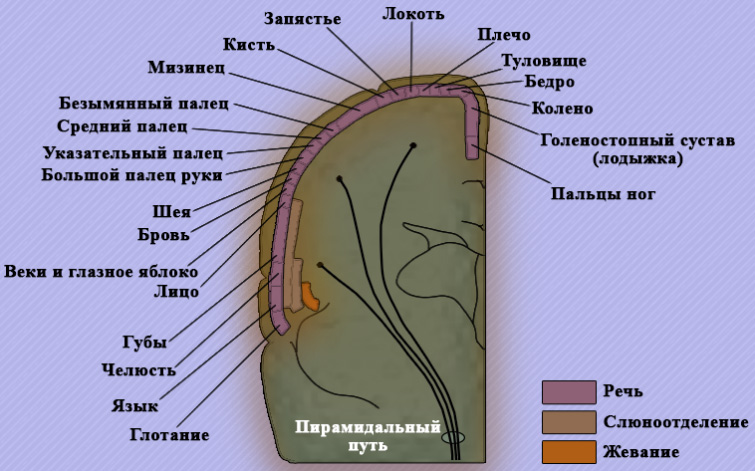

Пирамидные пути берут свое начало от двигательных нейронов V слоя моторной коры. Волокна пути пролегают через специальные структуры на вентральной поверхности продолговатого мозга – пирамиды (отсюда, собственно, и происходит их название). Пирамидные пути содержат примерно 2 миллиона нервных волокон, которые проходят белое вещество головного мозга в составе лучистого венца, занимая во внутренней капсуле передние отделы задней ножки. В стволе головного мозга пирамидные пути компактно расположены в среднем и продолговатом мозге, а достигая моста они разветвляются на ряд пучков (в том числе и на пучки, связывающих мост с мозжечком; рисунок 2). Достигая продолговатого мозга около 75% этих волокон пролегают в спинной мозг.

Рисунок 2. Пирамидный тракт

На уровне пирамид (на границе продолговатого и спинного мозга) корково-спинальный путь частично перекрещивается (в результате примерно 80% волокон этого пути переходят на противоположную сторону, где уже в составе латерального корково-спинномозгового пути (tractus corticospinalis lateralis) спускается в боковых канатиках, по ходу отдавая коллатерали к передним рогам каждого сегмента спинного мозга). В медиальных отделах к шейным и грудным сегмента проходят короткие волокна, а в латеральных отделах – более длинные волокна (в соответствии с законом эксцентрического расположения волокон Ауэрбаха-Флатау).

Передний корково-мозговой путь (tractus corticospinalis anterior), образованный из неперекрещенных волокон, проходит в передних канатиках. Волокна этого пути вместе с передней белой спайкой на сегментарных уровнях тоже переходят на противоположную сторону (отметим, что некоторая часть из этих волокон остается ипсилатеральной). Примерно 80% волокон взаимодействуют с моторными нейронами посредством вставочных нейронов передних рогов спинного мозга. И только 20% волокон, иннервирующих мускулатуру предплечья и кисти, имеют непосредственную связь (без посредников) с большими α-мотонейронами передних рогов, тем самым обеспечивая мелкомоторные (точные и тонкие) движения рук.

Менее 25% кортикоспинальных волокон обеспечивают проведение импульсов со скоростью более 25 метров в секунду (быстропроводящие, толстые миелинизированные волокна). Такие волокна обеспечивают высокоамплитудные движения конечностей. Остальная, большая часть нервных волокон – тонкие и медленно проводят импульсы (со скоростью около 1-2 метра в секунду), обеспечивая точные мелкомоторные движения.

Нейрональная активность обеспечивает регуляцию силу, частоту и длительность сокращений мускулатуры. Таким образом, пирамидальная система также выполняет антигравитационную функцию, позволяя организму приспособится к силе притяжения путем постоянной активации тонуса мышц-разгибателей и ингибированием мышц сгибателей.

Преддверно-спинномозговой путь пролегает без перекреста от ядра Дейтерса (латерального вестибулярного ядра, которое принадлежит VIII паре черепно-мозговых нервов; см статью «Черепно-Мозговые Нервы. Общие сведения») к клеткам передних рогов спинного мозга. Активирующие и тормозные ретикуло-спинальные тракты начинаются от ствола головного мозга и среднего мозга (рисунок 3).

Рисунок 3. Нисходящие пути спинного мозга